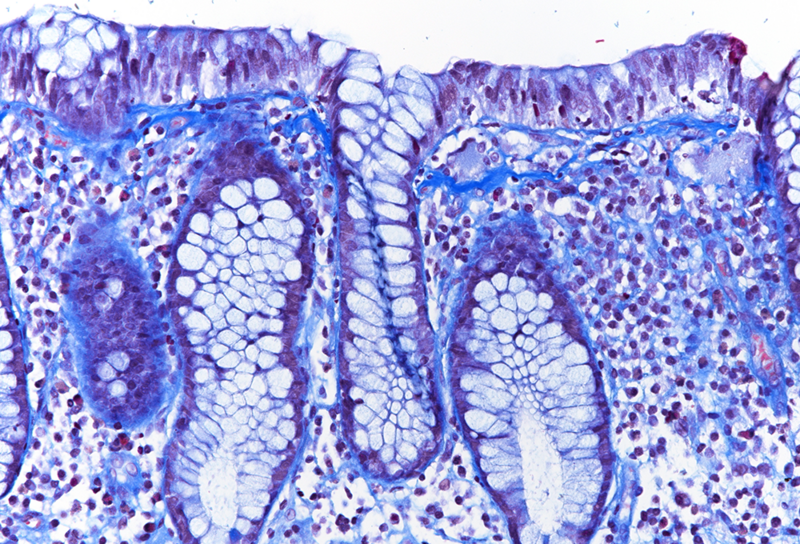

Colon biopsies from a 66-year-old male with chronic diarrhoea.

Collagenous colitis with giant cells.

Histologic examination showed irregularly flattened large-bowel mucosa with diffusely increased inflammation in the lamina propria, the inflammatory infiltrate consisting of plasma cells, lymphocytes and eosinophils. In all biopsies, a prominent, irregularly thickened (> 10 µm) collagen band was observed under the surface epithelium (Panel A), which could be highlighted by modified trichrome staining (CAB; Panel B). The surface epithelium was detached and showed degenerative changes. No crypt architectural distortion or metaplastic changes were observed, and no signs of active inflammation were present. Interestingly, several multinucleated giant cells were seen in the lamina propria close to the thickened subepithelial collagen band (Panels C-D).